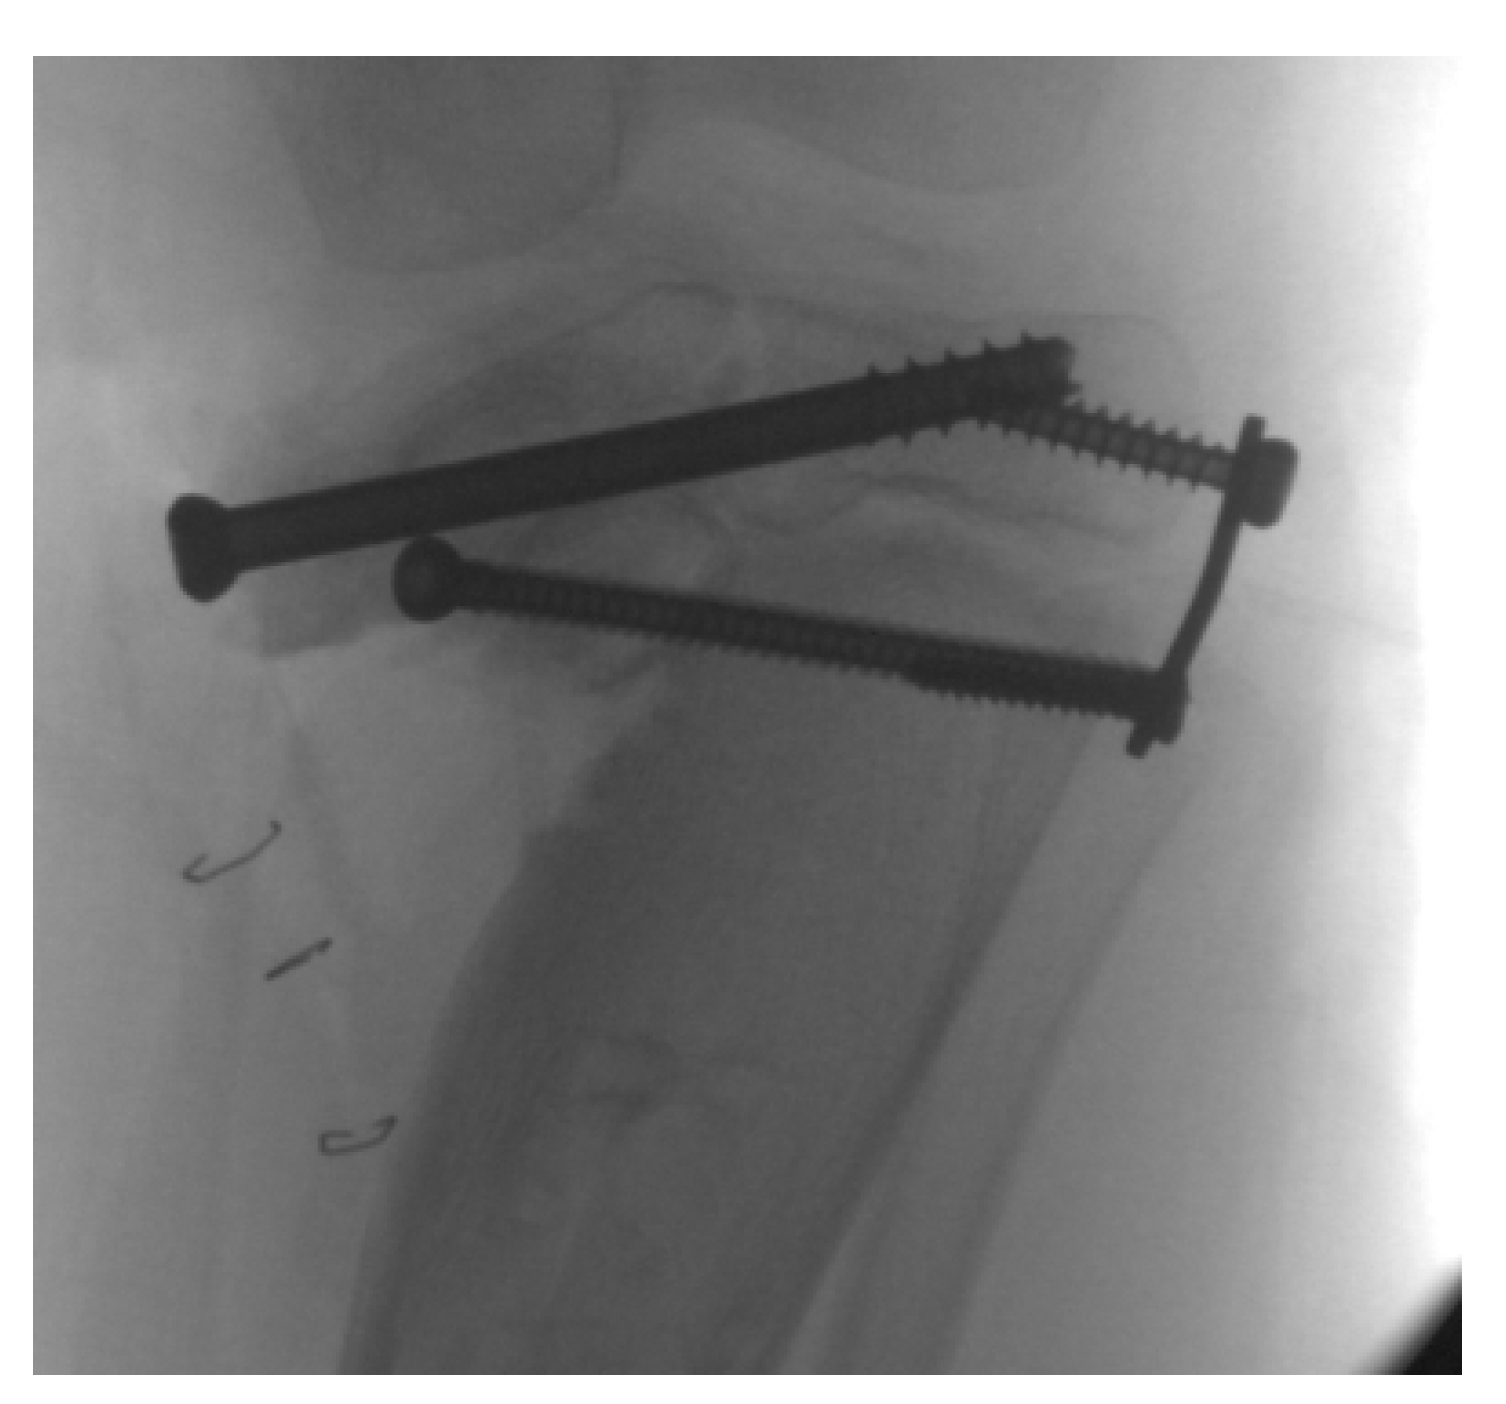

14. Hemi-Plateau Elevation Osteotomy

15. Combined Osteotomies